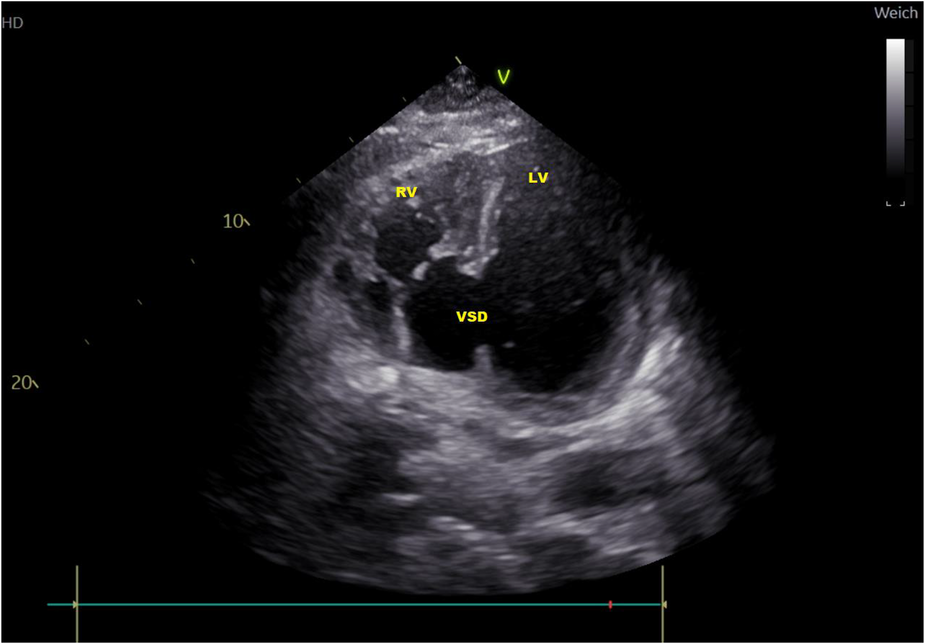

Figure 2

Transthoracic echocardiography atypical two-chamber view: ventricular septal defect (VSD), loaded left and right ventricle (LV, RV).

In subsequent echocardiography and cardiac computed tomography, the full dimensions of the ventricular septum defect were visualized. We discussed the VSD extensively with our adult and pediatric cardiologist colleagues and our congenital cardiac surgeons. Since dimensions were measured with 4.9 × 5 cm and its very close localization to the atrioventricular valve area (Figures 1, 2) not leaving a sufficient rim for placing either sutures or patch-sutures, the VSD was considered untreatable. In light of very few prospects for success, we considered a surgical VSD exploration and attempt of closure as way too risky for the patient.